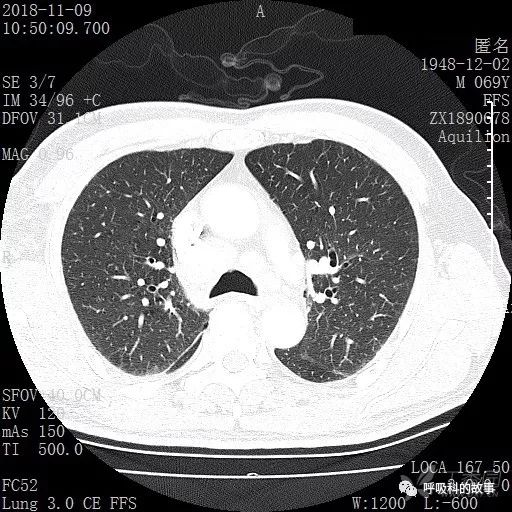

胸部增强CT示右肺门占位伴远端阻塞性肺炎,纵膈、右肺门、右侧颈根部、右侧腋下及肝门部肿大淋巴结。两侧胸腔少量积液。

肺窗CT